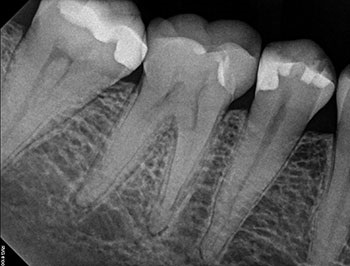

Case 12: Active irrigation

This patient presented for a second opinion after their dentist recommended extraction because of a VRF in the mesial root. The mesial root was surrounded by a U-shaped lesion, had a probing defect to the apex and all the canals were shaped with large flares. After discussing the possibility of VRF with the patient, re-treatment was recommended and accepted. No VRF was seen internally. Re-treatment was completed in a single visit, utilizing active irrigation and multisonic GentleWave technology. Complete healing occurred.

Fig.49: Postop PA.